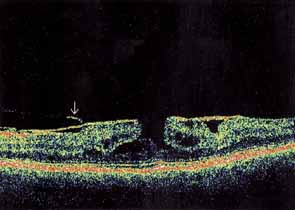

Optical coherence tomography or OCT is a relatively new tool used to diagnose macular lesions. It provides a unique view of the vitreoretinal architecture. OCT is particularly useful in diagnosing lamellar holes. With improvements in resolution and more widespread use, OCT will lead to new advances in the diagnosis and pathogenesis of macular holes (Fig. 2).

|

Some authors have commented on the importance of a posterior vitreous detachment in the pathogenesis of a macular hole.34,35 It is difficult to determine the vitreoretinal relationship preoperatively, even with careful slit-lamp evaluation. OCT testing can sometimes be helpful. However, the vitreomacular relationships are more accurately determined intraoperatively with use of oblique intraocular illumination and by noting the effect of gentle tractional forces on the macula during the vitrectomy. In some cases, what was thought to be a posterior vitreous separation preoperatively was actually found to be a large, optically empty space (Fig. 3).